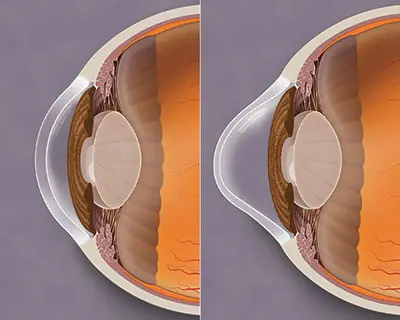

Queratocono

Esta condición puede ocasionar una curvatura irregular de la córnea, lo que resulta en una visión borrosa, astigmatismo y sensibilidad a la luz. En Oculaser, ofrecemos tratamientos especializados para el queratocono, con el objetivo de mejorar la calidad visual y brindar una mejor calidad de vida a nuestros pacientes.

-Anillos intracorneales: Se colocan anillos delgados y flexibles en la córnea para remodelar su forma y corregir la deformidad. Esto puede ayudar a mejorar la visión y estabilizar el queratocono. En Oculaser contamos con la técnología de Femtosegundo y nuestros cirujanos son especializados en queratocono

–Cross-linking corneal: Es un procedimiento que fortalece la estructura corneal mediante la aplicación de vitamina B2 y luz ultravioleta. Esto ayuda a detener o ralentizar la progresión del queratocono.